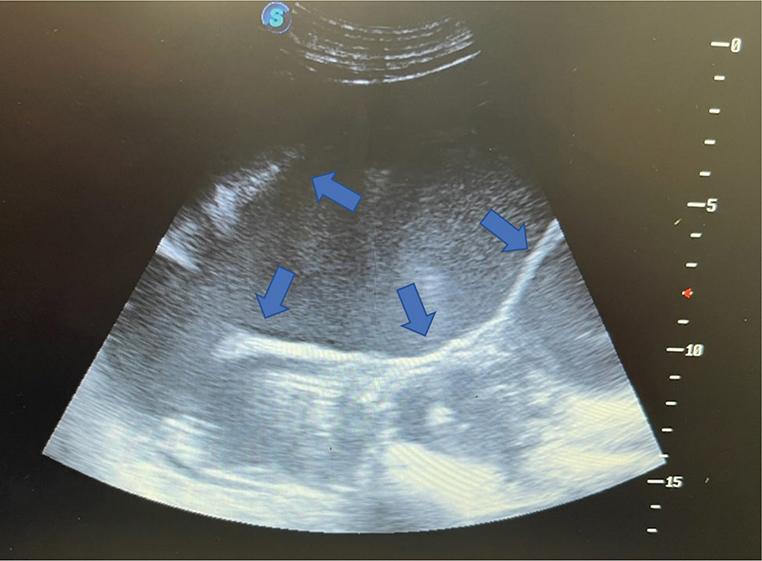

Figure 2.

Figure 2. Transabdominal ultrasonographic image of sow’s uterus at presentation (note distended uterine horns [blue arrows] filled with mildly echogenic fluid)